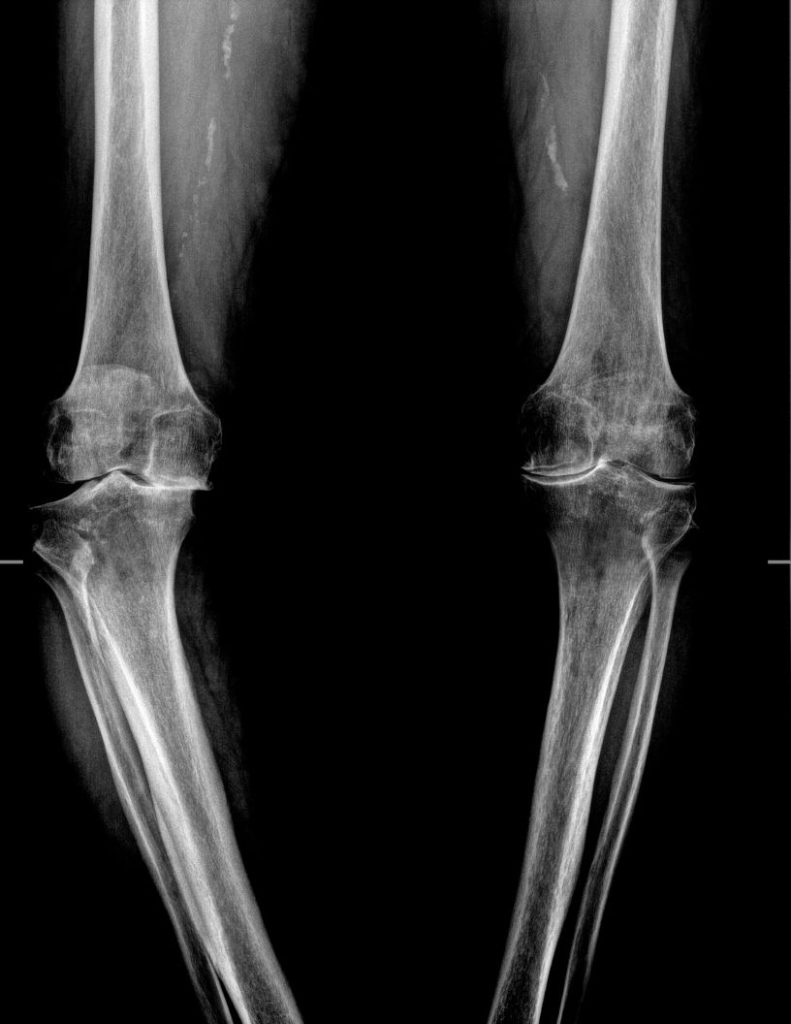

gonartrosi bilaterale

Prima